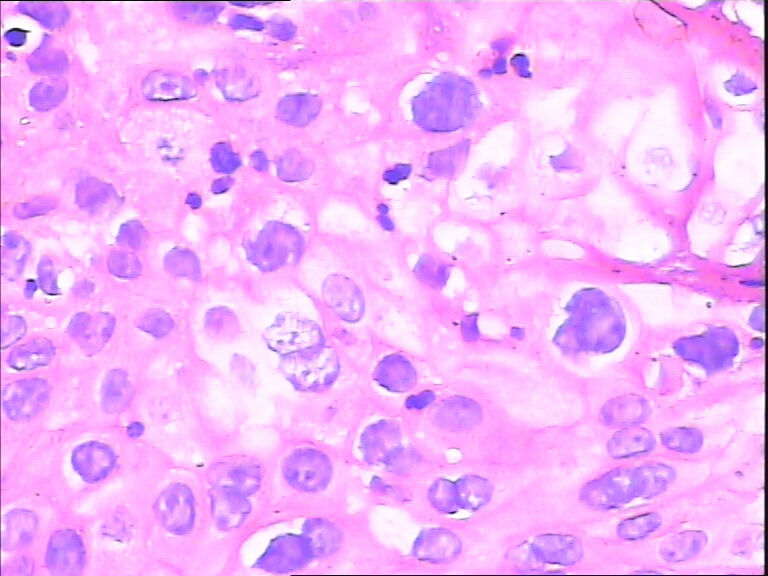

45y,触血,宫颈多点活检。